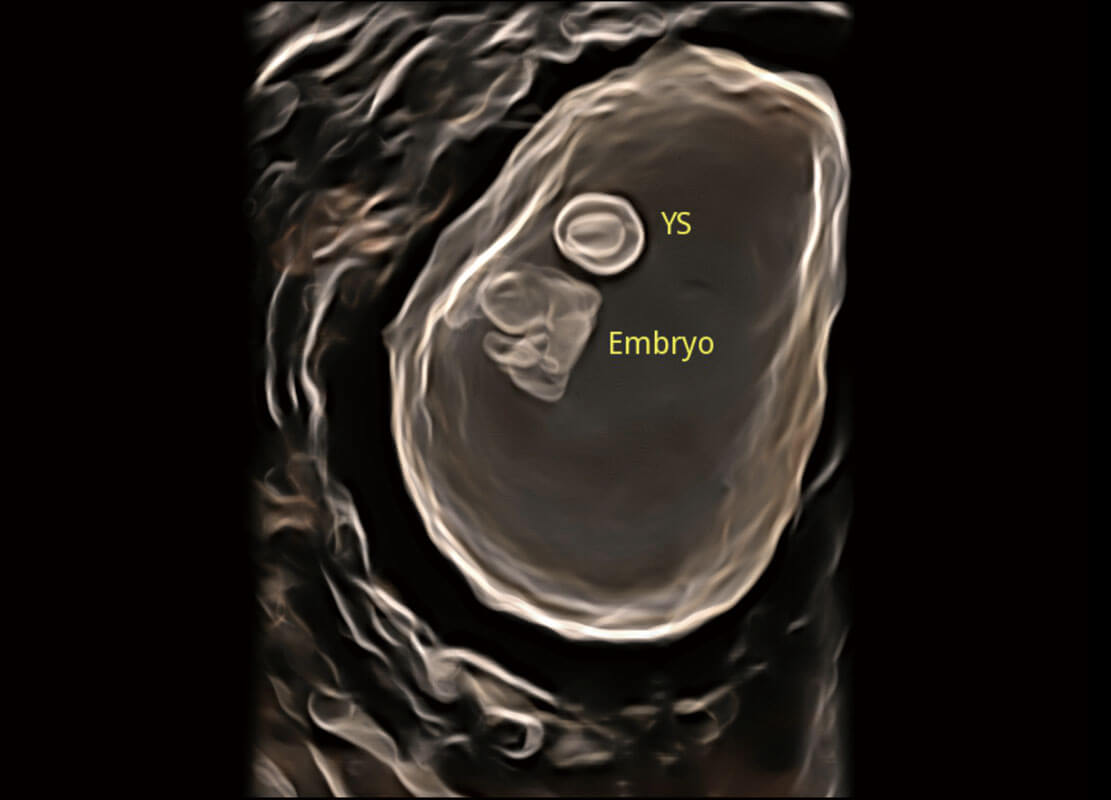

高分辨率容积成像-早孕胎儿

光影成像-孕囊